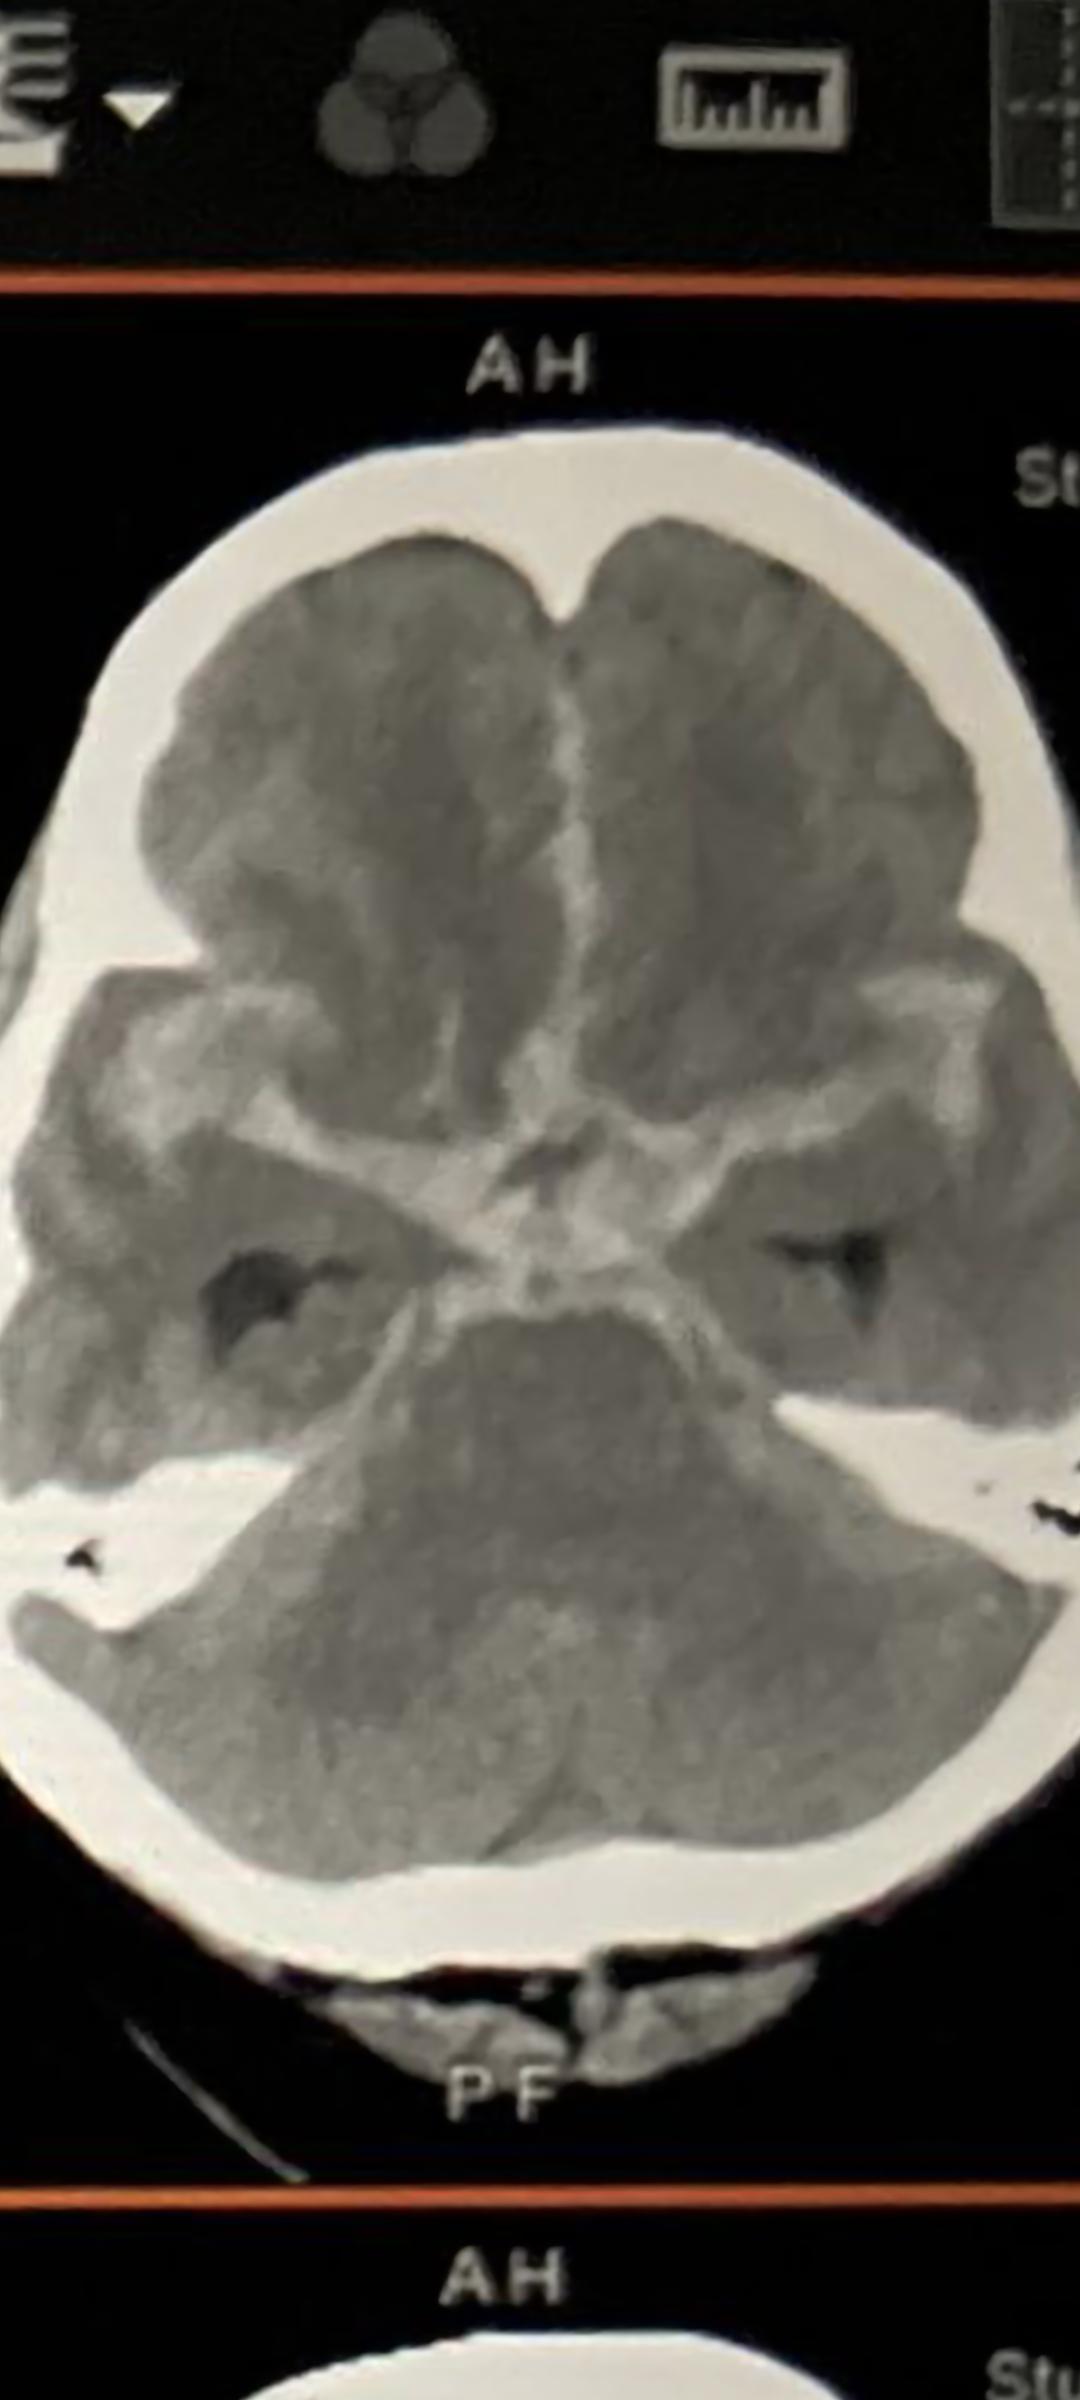

第二種頭痛是突發性頭痛,像一顆炸彈在腦內爆炸,患者通常形容該頭痛是人生經歷最突然和嚴重的頭痛,有些病人會同時感覺後頸痛。以上是蜘蛛膜下腔出血的病徵,原因多是由腦動脈瘤破裂導致。這種動脈瘤成因不明,大多在腦血管分支點發生,破裂前多毫無病徵,因為這些動脈瘤多是幾毫米直徑,對腦壓完全無影響。蜘蛛膜下腔出血是很嚴重的出血性中風,有1/3患者當場死亡,因為顱內壓急升導致心肺衰竭,另外1/3可到醫院治療但有不同程度的後遺症,最差可變成植物人,只有1/3病人出事後出現小量或沒有後遺症。所以有以上病徵,要馬上找醫生檢查,延誤診治可導致二次出血,死亡率高達50%。入院後的手術治療只能防止二次出血和可能出現的後遺症,例如腦積水。雖說這病成因不明,但其中多囊腎病患者有較大機會患動脈瘤病。以上兩種頭痛不能掉以輕心,稍有延誤診治可帶來不可逆轉的後遺症。